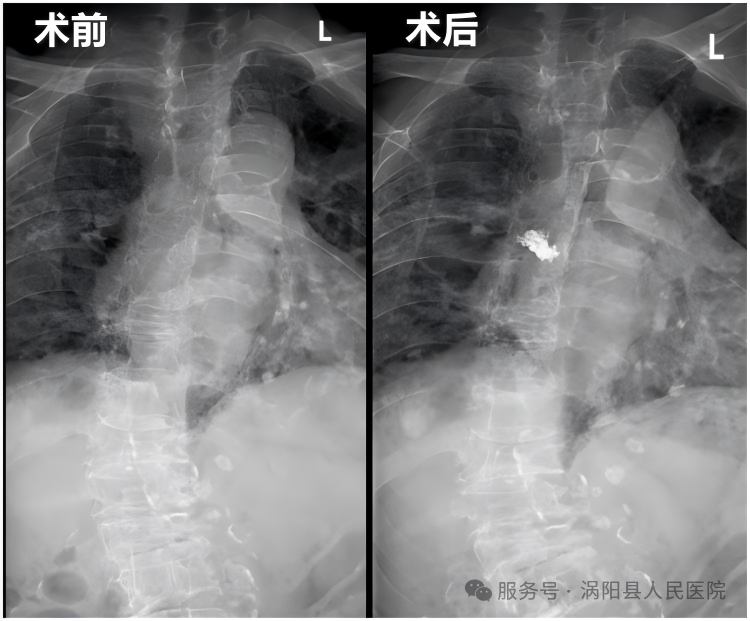

近日,我院骨科三病区成功为一名85岁高龄、伴有严重胸椎侧弯后凸畸形的胸椎骨折患者实施了微创手术,术后次日便能下床活动,目前已康复出院。

该患者因严重的骨质疏松导致胸6椎体压缩性骨折,剧烈的胸背疼痛让她卧床不起,日常生活受到极大影响。更棘手的是,患者还合并有长期的脊柱侧弯和后凸畸形,这使得常规手术创伤大、风险极高,对麻醉和手术技术都是巨大的挑战。

面对如此复杂的病情,我院骨科团队联合多学科经过周密评估,最终为患者选定了经皮椎体后凸成形术(PKP)。这是一种先进的微创治疗技术,仅通过背部一个约5毫米的“钥匙孔”小切口,将精细的工作通道置入骨折的椎体内,然后注入适量的“骨水泥”,迅速稳定并强化受损的椎体。

手术过程顺利,患者术后原本剧烈的疼痛感基本消失。术后第二天,在医护人员的指导下,老人已能佩戴护具下床站立和缓慢行走,脸上露出的笑容,让家属对此感激不已。